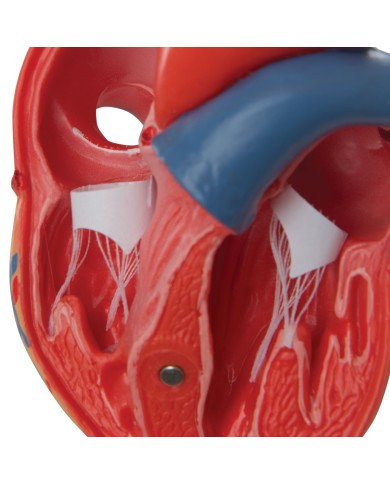

Modello di cuore di alta qualità scomponibile in 5 parti

Modello di cuore di alta qualità scomponibile in 5 parti

La parete anteriore del cuore è staccabile per poter vedere i ventricoli.